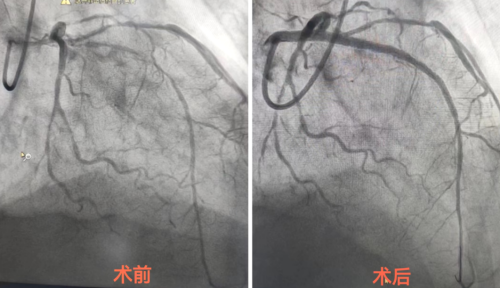

今年75岁的刘女士,2年前开始出现胸闷、气促、心前区闷胀感,未引起重视,近2月胸闷、气促较频繁才来就诊。为明确病因,行冠状动脉造影后,诊断为:冠状动脉粥样硬化性心脏病,三支血管病变,左前降支近中段弥漫性病变且360°严重钙化。

检查结果意味着患者的心脏冠状动脉出现了严重问题,左前降支全程弥漫性重度钙化、近中段狭窄,球囊通过困难,扩张极不充分,无法正常植入支架。

术中,叶国红副主任医师通过球囊低压扩张,向血管病变处发射非聚焦、低能量、脉冲式的冲击波,安全地碎裂浅、深层钙化,予前降支近中段植入支架1枚,术后造影见局部狭窄消失,支架膨胀完全,贴壁良好。

手术非常成功,血管病变处狭窄明显缓解,刘女士各项生命体征平稳,随后返回心血管内科继续治疗,并于4天后顺利出院。